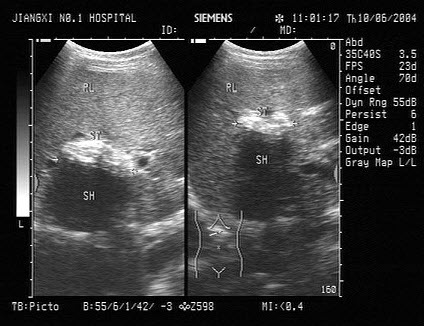

23、单项选择题

女,20岁,上腹痛并呕吐,入院诊断“急性胰腺炎”。结合超声声像图,诊断为()

A.胰腺脓肿

B.胰腺假性囊肿

C.胰腺囊肿

D.胰囊肿性腺瘤

E.胰腺癌